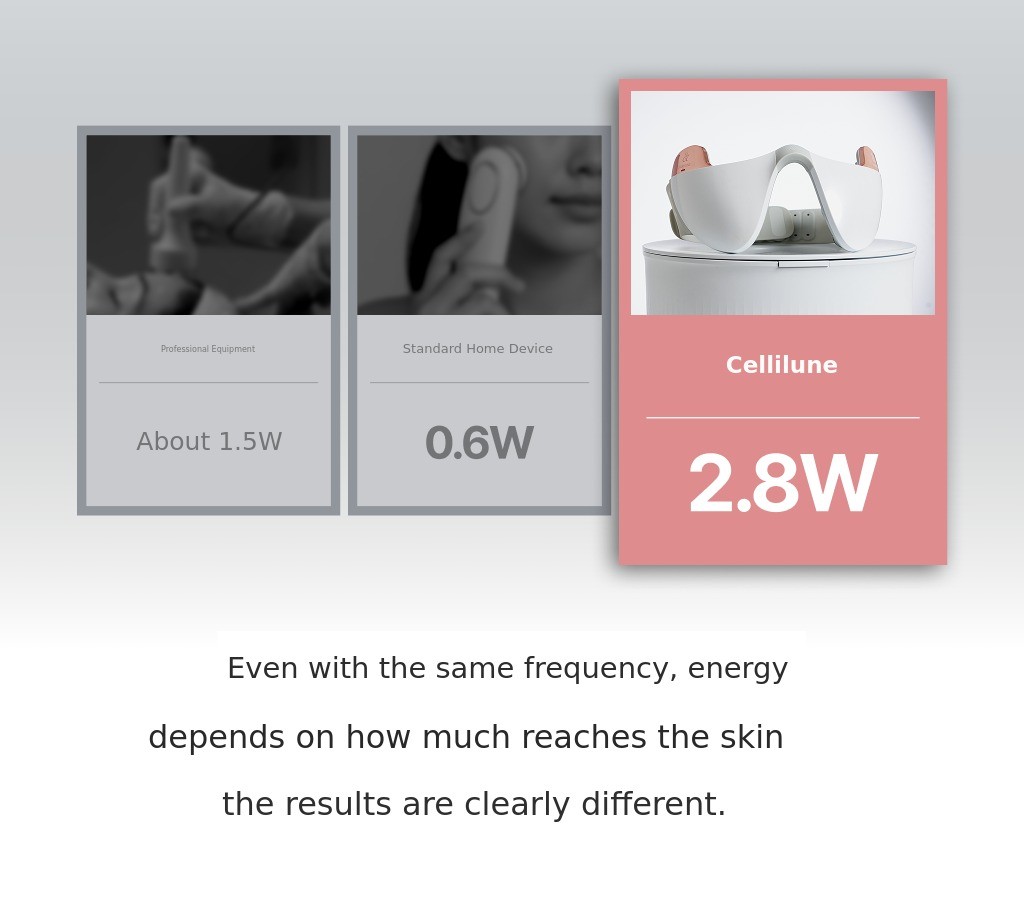

I also tried countless devices myself and felt their limitations.The energy is weak, the usage is cumbersome, and above all, the 'effect' is lacking. Especially, there were limitations to the method of 'rubbing' the face every day with a single small head.

And for over two years, I focused on the core of LDM technology,3MHz + 10MHz ultrasound, and12 titanium heads that replicate expert hand techniques, medical-grade output, a mask-type structure that anyone can easily use and personally designed them.

The comfort of not having to rub every day, the power to reach the real dermis with medical-grade output, and above all,the experience of enjoying that feeling you get at the clinic, right at home, We put all of that into one device.